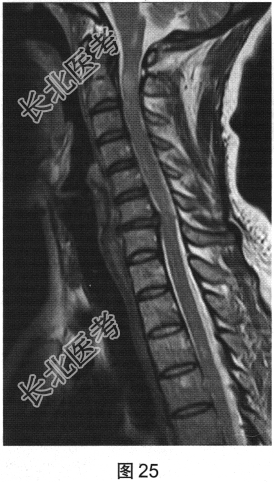

- 多项选择题2.[提示]患者行脊柱MRI平扫及增强检查,如图25、图26所示。关于MRI检查结果, 描述正确的是( )

A、脊髓未见异常

B、颈髓T2WI可见多发片状高信号影

C、脊髓空洞

D、部分胸髓T2WI可见多发片状高信号影

E、脊髓肿胀

F、MRI增强检查可见小片状强化

- 多项选择题3.根据脊髓和颅脑MRI表现,病变应诊断为( )

D、多发性硬化